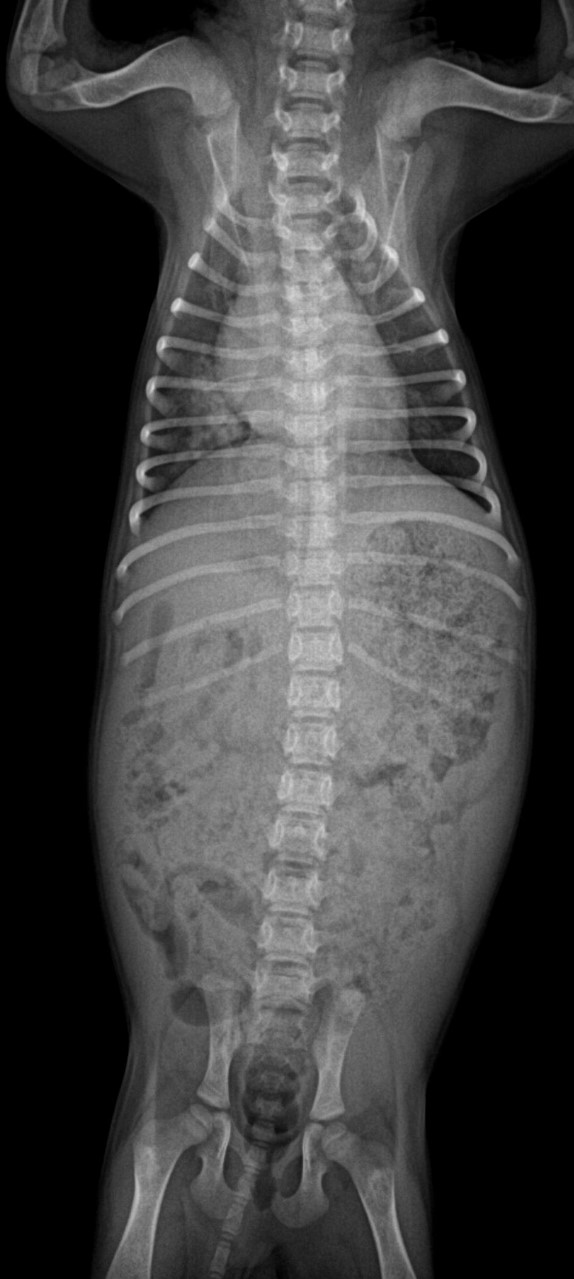

청진상 이상음이 들릴 수 있으며 (쌕쌕거리는 소리, 딱딱거리는 소리, 펑하는 소리 등), 방사선(X-ray) 검사가

진단에 유용합니다.

호흡이 빠르고 열이 있어서 방사선 검사와 혈액 검사를 진행했습니다.

검사결과 백혈구 숫자증가, 염증지표(CRP)의 상승, 방사선상 폐침윤이 확인되어 안타깝게도 폐렴이 진단되었습니다.